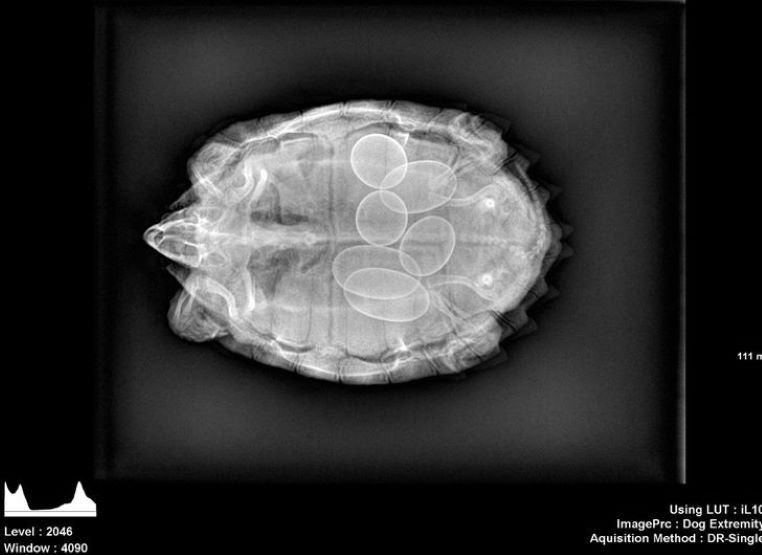

Une tortue enceinte

galerie-rayon-x-tortue-enceinte